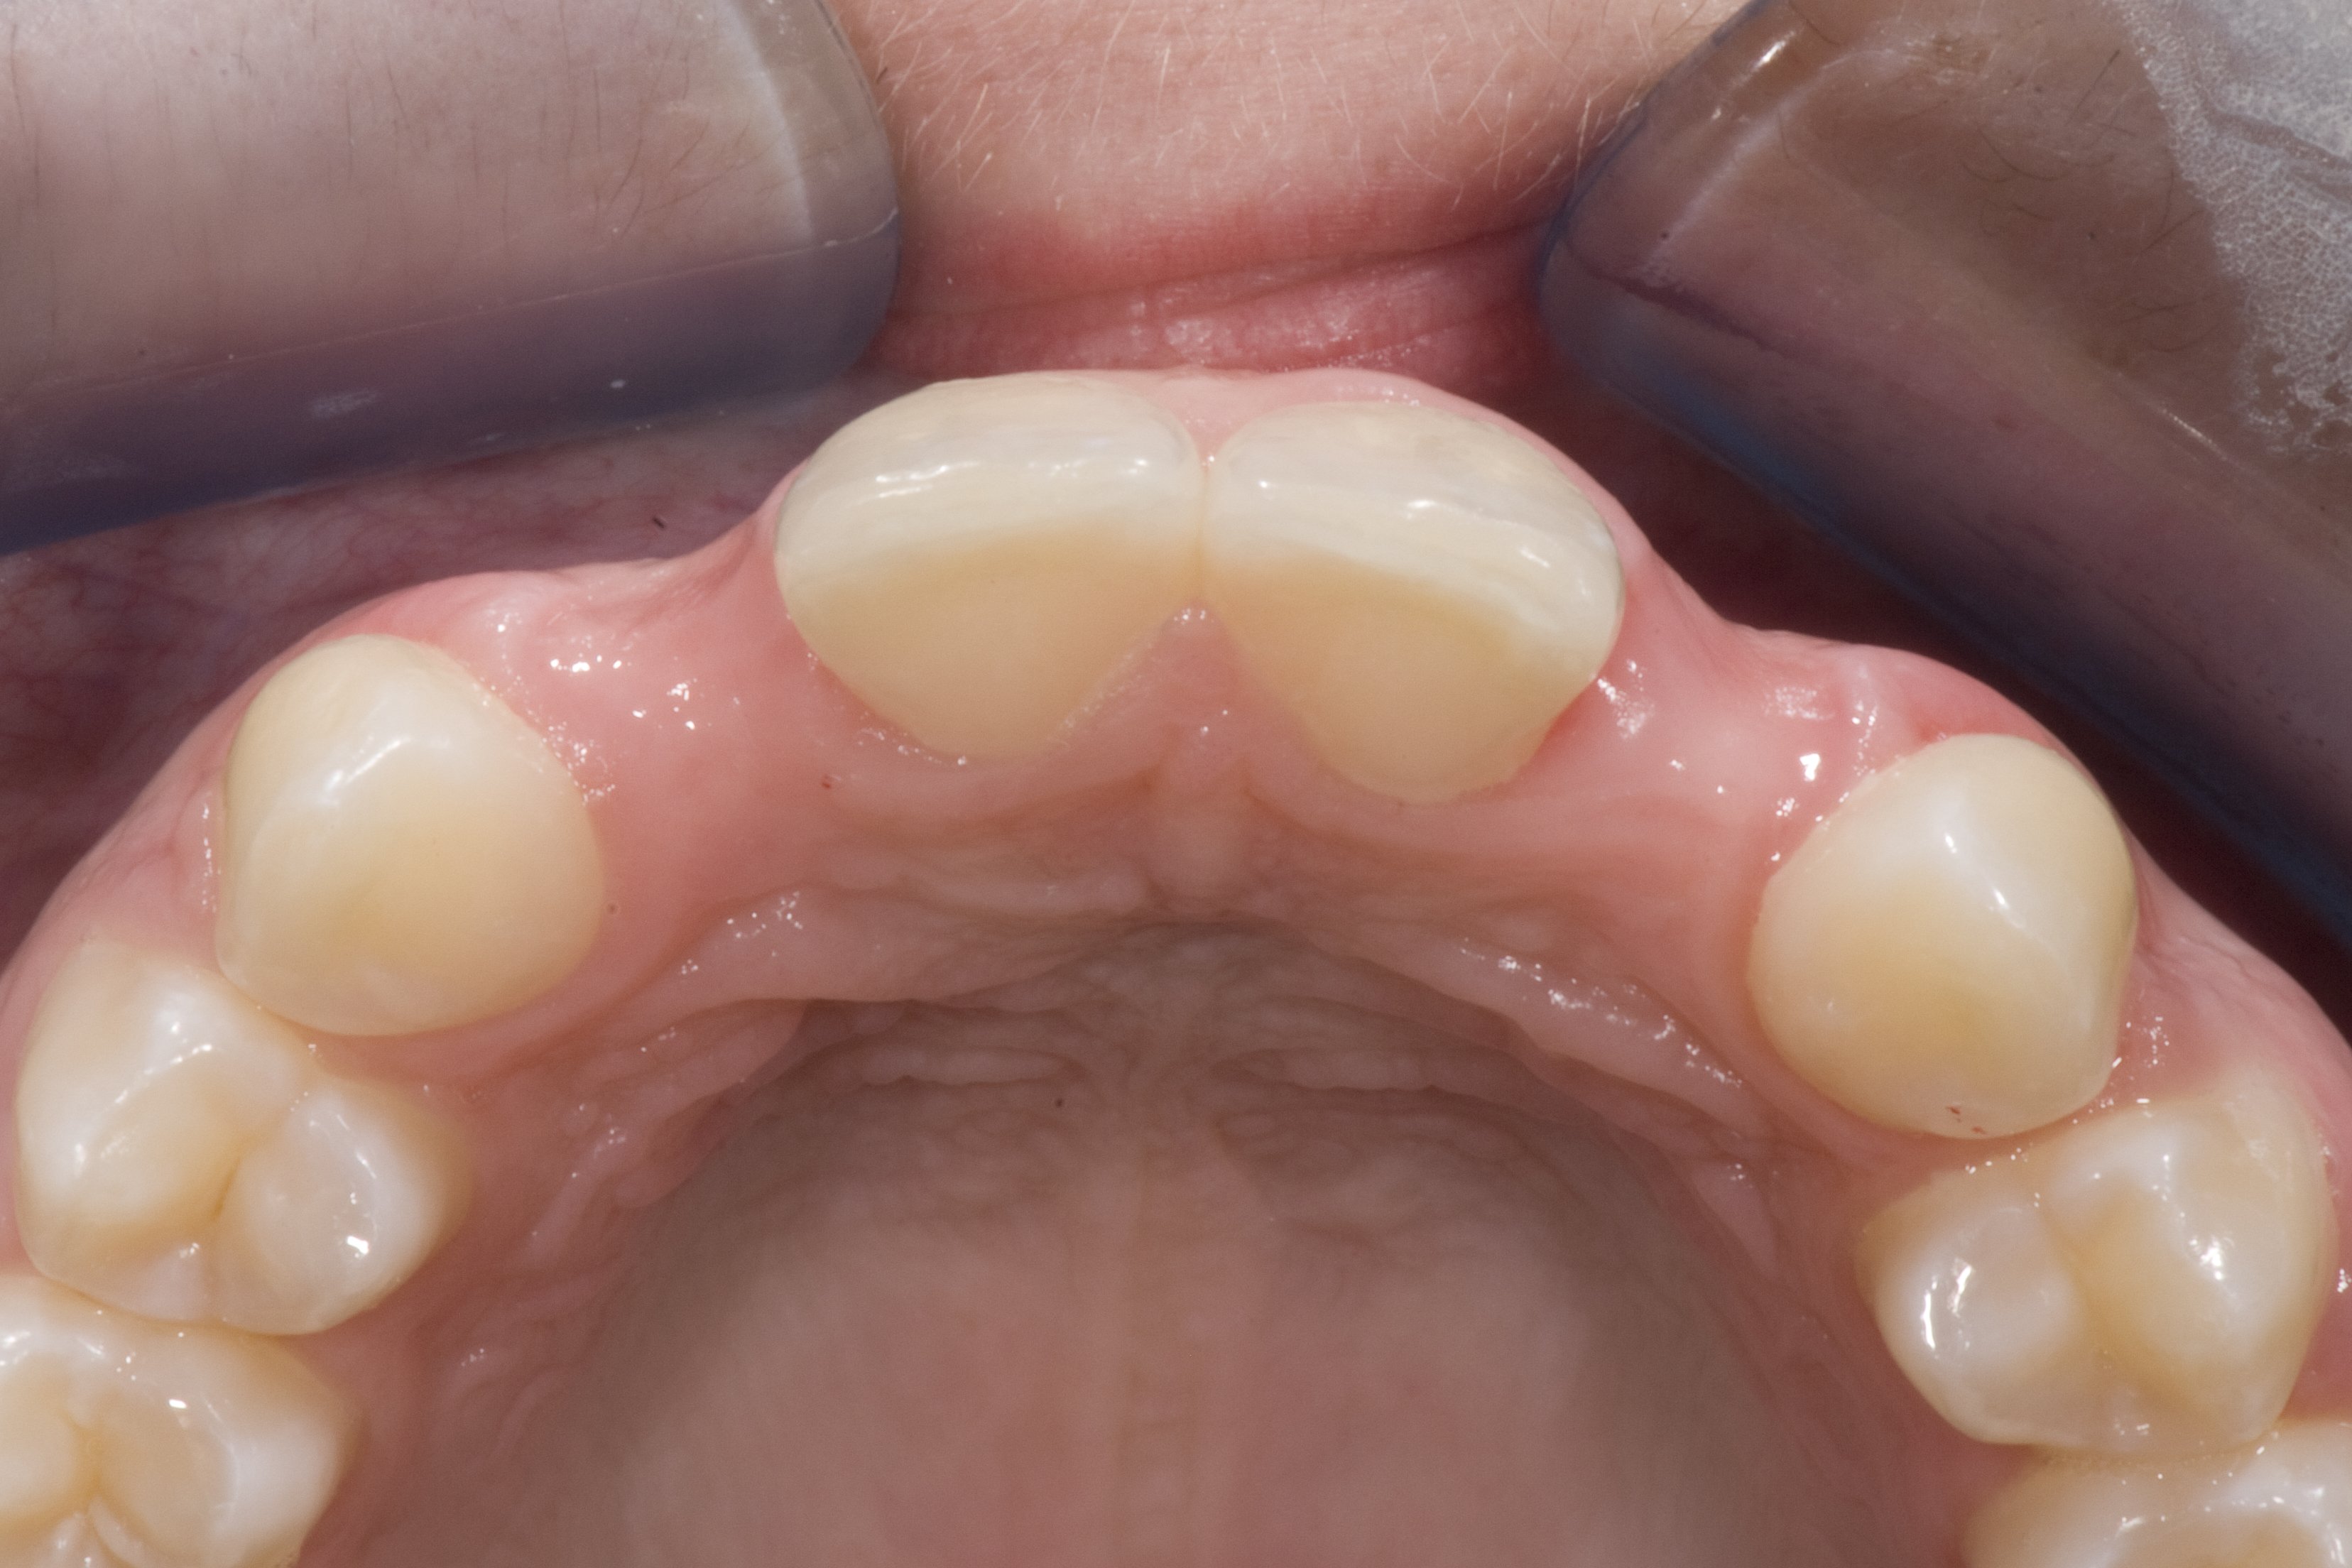

(14.) Occlusal view. Some form of augmentation would be needed if implants were being considered.

Figure 14